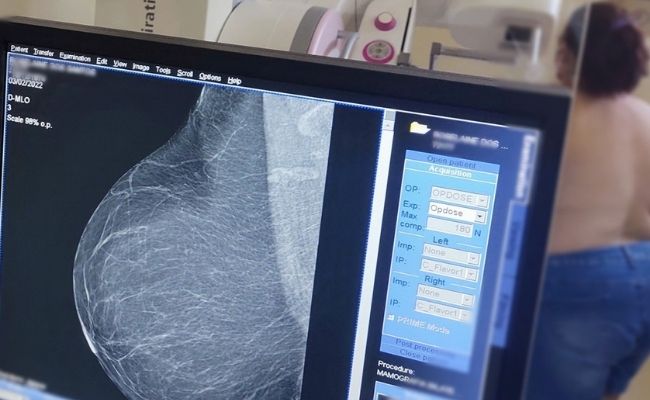

Novo Hamburgo reforça prevenção ao câncer de mama com novas diretrizes para mamografia

Outubro chega trazendo a cor rosa como símbolo da prevenção e do diagnóstico precoce do câncer de mama. Em Novo Hamburgo, o mês ganha ainda mais relevância diante das novas diretrizes nacionais para a mamografia anunciadas pelo Ministério da Saúde em setembro deste ano.

Desde 2022, o Município não possui fila de espera para o exame e, entre janeiro de 2023 e agosto de 2025, já foram realizadas 14.819 mamografias no Centro Municipal de Imagens. Do total, 10.778 foram em mulheres de 50 a 69 anos — faixa etária que, até setembro, era a indicada para rastreamento sistemático. Outras 4.041 mulheres, fora dessa faixa etária, também foram atendidas conforme indicação clínica ou solicitação médica

Com a atualização da diretriz nacional, a mamografia passa a ser oferecida também a mulheres entre 40 e 49 anos, mediante decisão compartilhada entre paciente e profissional de saúde. Além disso, a faixa etária de rastreamento sistemático foi ampliada até os 74 anos.